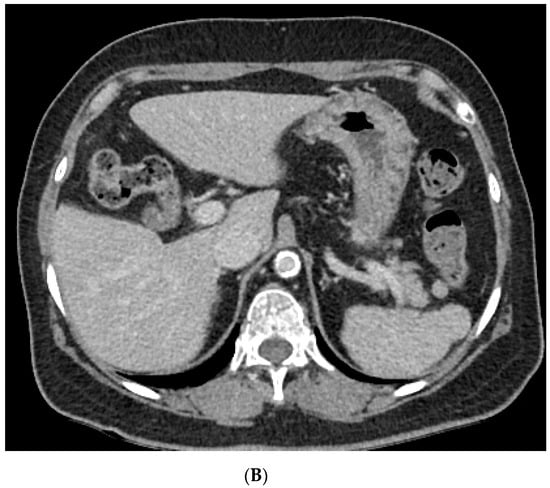

Figure 1.

Abdominal computed tomography (CT) image. (A) Axial CT image on day 1, illustrating wedge-shaped splenic infarcts (white arrow). (B) Axial CT image 2 months later, showing an improved splenic infarction.

A 74-year-old female patient presented to the emergency department of Kyung Hee University Medical Center because of dizziness and generalized weakness that started 2 days prior. The patient had a history of old cerebral infarction and was taking oral medications for hypertension and dyslipidemia. Brain magnetic resonance imaging (MRI) revealed an acute focal infarction in the right basal ganglia. At that time, in the laboratory examinations, the erythrocyte sedimentation rate (ESR) was 74 mm/h (normal range, <20 mm/h) and C-reactive protein (CRP) level was 6.61 mg/dL (<0.5 mg/dL) Aspirin was prescribed to the patient. One month later, the patient was admitted to our neurology clinic because of weakness in her left arm and numbness in both hands. MRI revealed no diffusion-restricted lesion in the brain. Physical examination revealed no remarkable findings except for paresthesia in the left hand. The patient’s motor power of four limbs were normal (grade 5). Her initial chest radiograph was normal. Her laboratory examination results showed a white blood cell count of 9.79 × 109/L (76% neutrophils), ESR of 120 mm/h, and CRP level of 18.44 mg/dL. However, she had no fever. Her serum creatinine level (0.92 mg/dL) and estimated glomerular filtration rate (GFR; 63.59 mL/min per 1.73 m2) were within the normal ranges. No proteinuria was identified. Chest computed tomography (CT) and abdominal CT were performed to exclude hidden malignancy. Chest CT revealed a subpleural nodule measuring approximately 1.5 cm in the right lower lobe. Abdominal CT revealed multiple small ill-defined low-attenuated lesions in the spleen nodules (Figure 1). Her thrombophilia screening test result was negative. The Padua prediction score was 2, in the low risk.Her echocardiography was normal and 24-hour Holter monitoring revealed normal sinus rhythm. Nerve conduction tests revealed sensorimotor polyneuropathy. The myeloperoxidase (MPO)-ANCA test result was positive (5.10 index). Percutaneous needle biopsy of the pulmonary nodule was performed first; however, the pathological results showed only focal acute inflammatory cell infiltration, with no evidence of malignancy. The second biopsy of the sural nerve demonstrated perivascular inflammatory cell infiltration and necrotizing vasculitis. These findings were consistent with vasculitic peripheral neuropathy. By considering the results of the MPO-ANCA test and the pathological profile of the sural nerve, the patient was diagnosed as having MPA-associated neuropathy with a splenic infarction and pulmonary inflammatory nodule. She received steroid pulse therapy (methylprednisolone, 125 mg/day for 3 days) on day 20 of hospitalization, followed by cyclophosphamide (500 mg/m2 every 4 weeks for six doses) with steroid maintenance therapy. She showed improvement after the steroid therapy. Her ESR level decreased to 49 mm/h and the CRP level decreased to 0.5 mg/dL. The peripheral numbness subsided slowly. After 1 month, the patient’s pancreatic enzyme levels (amylase, 192 U/L (23–85 U/L) and lipase 346 U/L (0–160 U/L)) were elevated without abdominal pain. Abdominal CT was performed to evaluate for pancreatitis and revealed improvement of the splenic lesion such as the infarction. The patient had an uneventful course for 5 months after the treatment.This study was approved by the Institutional Review Board (IRB) of Kyung Hee Medical Center, and the requirement for informed consent was waived (IRB 2020-12-083).